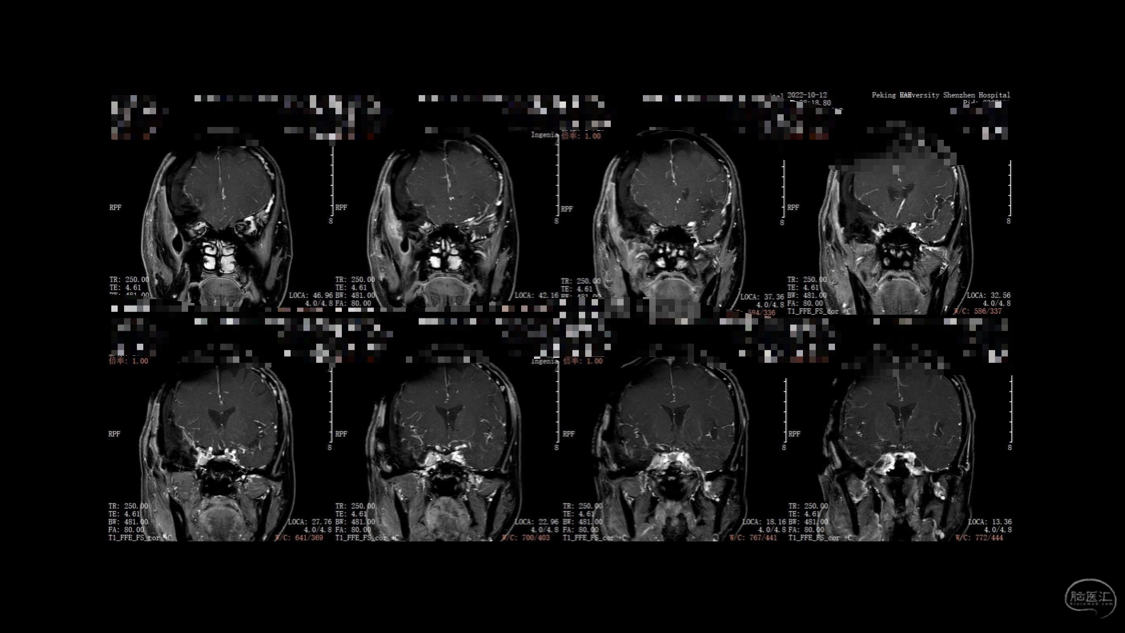

陈保东教授手术作品-右眶内及海绵窦旁孤立性纤维瘤